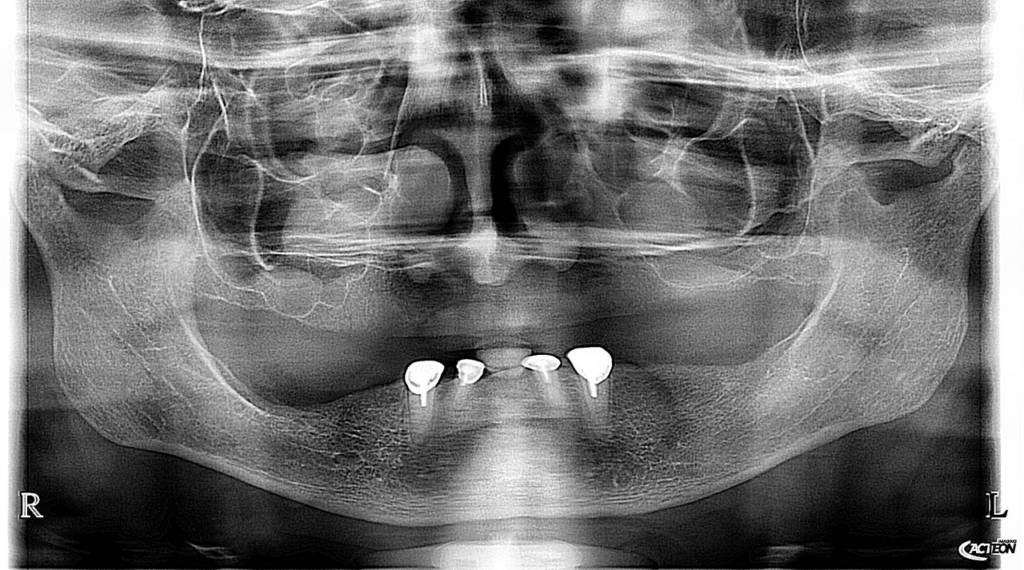

Pacienta in varsta de  65 ani, edentata total la maxilar si subtotal la mandibula la care s-a realizat o reabilitare protetica cu proteze mobile totale, la mandibula primind o supraproteza stabilizata pe magneti atasati unor cape pe dintii restanti. Protezele sunt armate cu plasa metalica individualizata pe forma crestelor restante pentru cresterea rezistentei mecanice a acestora.